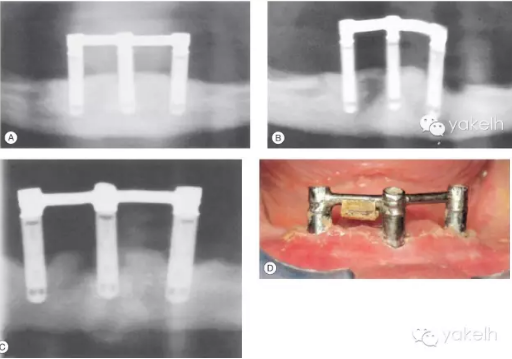

72歲女性患者,行下頜3顆種植體支持覆蓋義齒修復(fù)(圖.15A)。5年復(fù)查發(fā)現(xiàn)左側(cè)遠(yuǎn)中1顆種植體發(fā)生了種植體周圍炎(圖.15B)。在隨后的5年中,種植體周圍炎進(jìn)一步發(fā)展,在種植體周圍形成了彈坑樣的骨缺損(圖.15C)。

由于隨著患者年紀(jì)變大,身體越來越虛弱,而無法保持種植體周圍以及義齒下端的口腔衛(wèi)生,從而導(dǎo)致種植體周圍炎的易感性進(jìn)一步增加(圖.15D)。

對(duì)于種植體支持的覆蓋義齒而言,義齒內(nèi)陰性固位裝置的折斷也是經(jīng)常碰到的問題,盡管通過椅旁操作便可以進(jìn)行更換,但這仍然會(huì)給患者帶來麻煩。

圖.15 (A~C)這3張放射片間隔5年拍攝,顯示種植體周圍骨組織不斷喪失。 (D)口內(nèi)照顯示口腔衛(wèi)生差,種植體周圍軟組織存在炎癥。